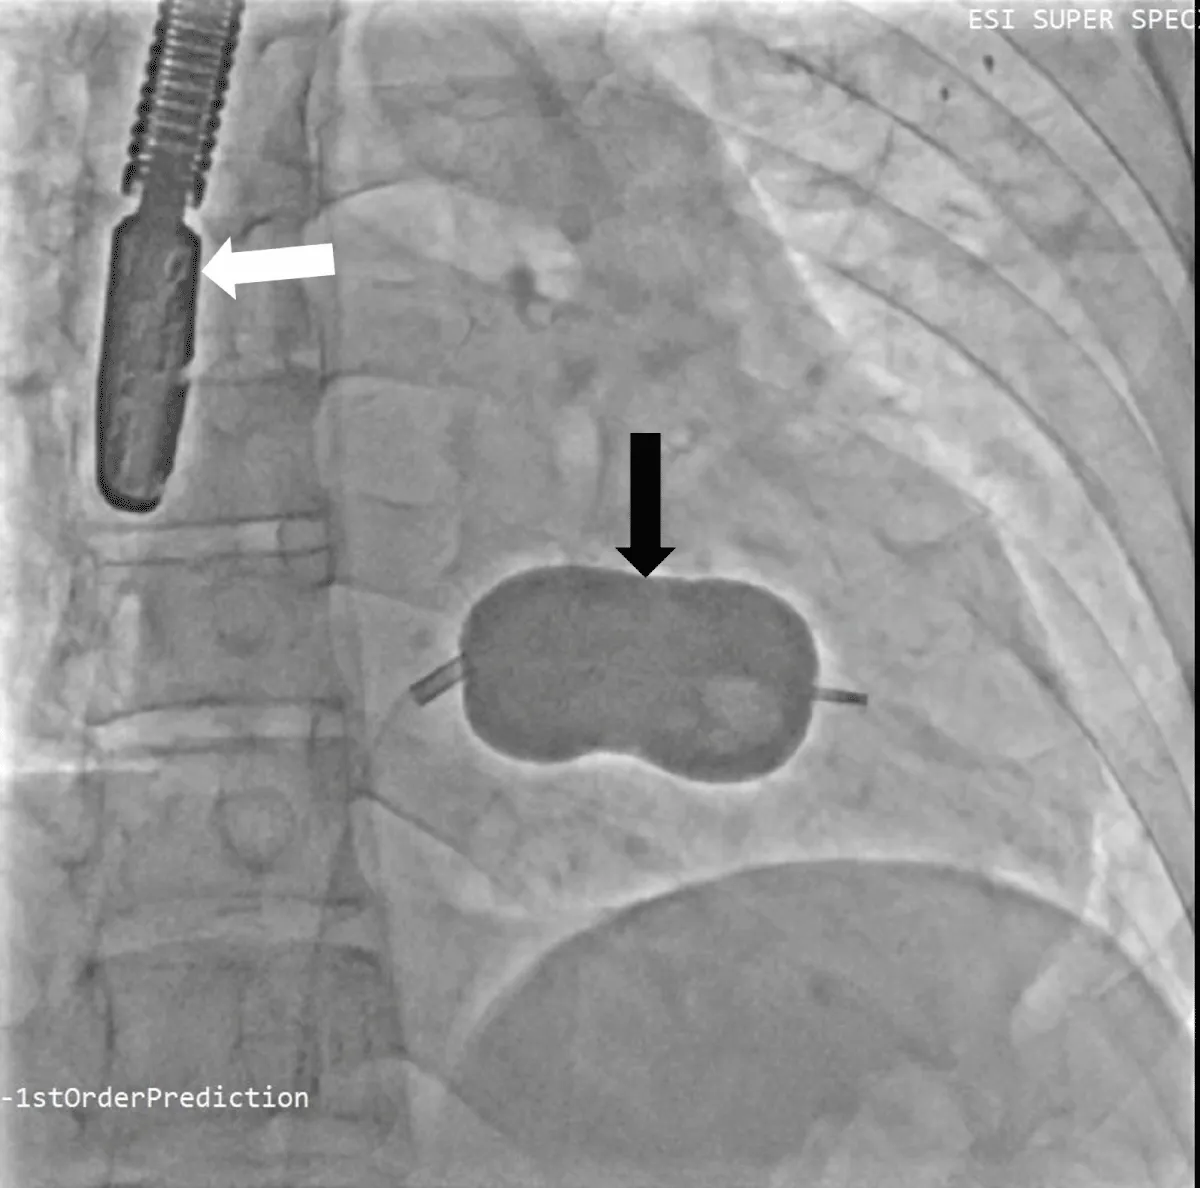

He was planned for double valve replacement (DVR), but the patient declined due to the high surgical risk. Therefore, he was considered for staged BMV and Transcatheter aortic valve replacement (TAVR). Pre-procedural planning was done for TAVR, and after ensuring the patency and adequacy of femoral vessels, he underwent a coronary angiogram (CAG), which showed normal coronaries. Following consent, the right femoral vein was accessed. A transseptal puncture was performed with a broken Brough needle, and the LA wire was parked. The MV was dilated with a 26 mm Inoue balloon (Figure 7), resulting in a reduction of the MV gradient from 24/10 mm Hg to 9/5 mm Hg and an increase in MV area from 0.9 cm2 to 1.6 cm2. There were no post-procedural complications. After 1 month, he underwent TAVI. Both right and left femoral artery access was obtained. Following pre-dilatation of the AV with an 18 mm balloon, TAVR was performed using a 26 mm balloon-expandable valve (Myval, Meril Lifesciences, Vapi, Gujarat, India) (Figure 8) (Video 3), followed by post-dilatation under accelerated right ventricular pacing (180 bpm). ECHO and final aortography showed no paravalvular leakage after device release (Figure 9).

Download Image

Figure 8: Fluoroscopic image of Balloon dilatation of the aortic valve (A) followed by aortic valve implantation (B) under right ventricular pacing.

Figure 9: Fluoroscopic image of aortic valve implantation without coronary compression after (A) and before the deployment (B).

Post-TAVR, the AV gradient was reduced from 98 →10 mm Hg. No procedural or post-procedural complications occurred. The hospital course was uncomplicated, and the patient was discharged after 4 days.